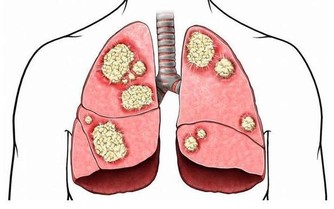

第三,本身存在相關疾病糖尿病或者泌尿科疾病的老年人,在排尿方面會出現異常,可能身上會出現尿騷味,也就會讓壬烯醛的味道與尿騷味相互結合,產生較為難聞的氣味。

3. 積極治療疾病

對於患有糖尿病或泌尿科疾病的人,一定要儘早治療,才能避免出現排尿異常相關問題。當然,在生活方面、飲食方面也是要多注意的,如此,更有利於避開老人味。